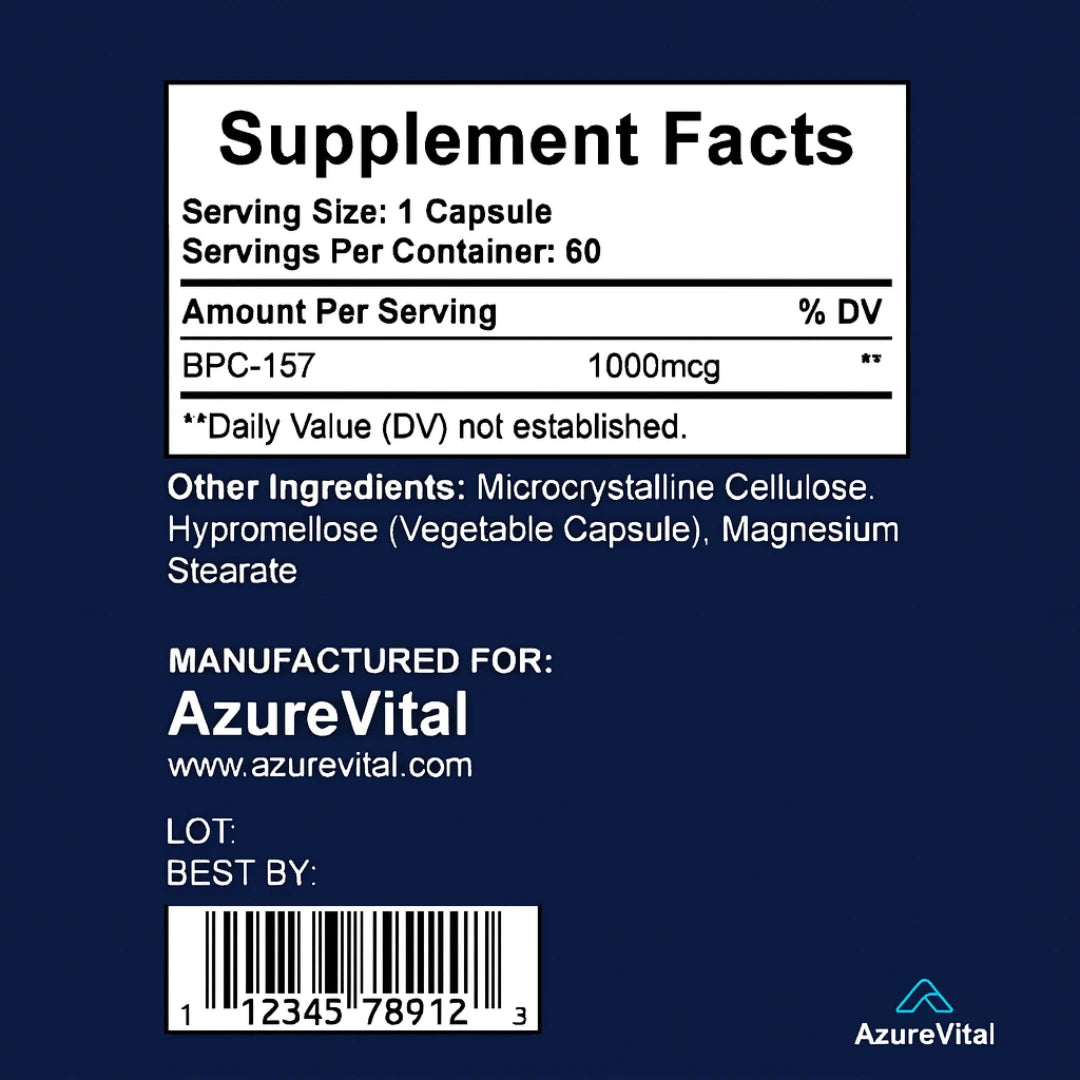

2. What are the ingredients in BPC-157?

2. What are the ingredients in BPC-157?

Each serving contains 1000mcg of BPC-157 , which includes amino acids such as L-Valine, L-Glutamine, L-Glycine, L-Proline, L-Lysine, and others. The capsule is made from vegetable cellulose, and the formula is vegan, non-GMO, sugar-free, and dairy-free.

The recommended serving is 1000mcg daily, typically taken as 1-2 capsules per day (based on the full-dose version shown in the label). For your version, use the suggested dose on your packaging or consult with your healthcare provider.

Transparent Labeling |